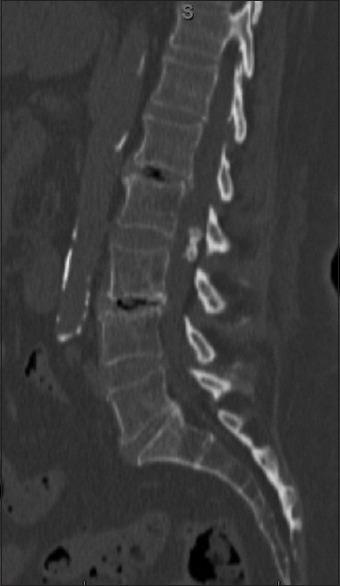

We present the case of a 72-year-old female who had longstanding history of low back pain that exacerbated 20 days prior to the presentation to the emergency room with a frank cauda equina syndrome. The lumbar computed tomography scan showed a hyperdense lesion, suggestive of calcified tumor, whereas the magnetic resonance imaging revealed a hypointense lesion on theT1 and T2-weighted images, without contrast enhancement or edema on fluid-attenuated inversion recovery. She underwent an emergent L2-L4 laminectomy and L3-L4 discectomy with resection of L2 intradural tumor, following which she regained normal function.

我们报告一例72岁女性,有长期腰痛病史,在因明显的马尾神经综合征就诊于急诊室前20天病情加重。腰椎计算机断层扫描显示高密度病变,提示钙化肿瘤,而磁共振成像在T1加权和T2加权图像上显示低信号病变,在液体衰减反转恢复序列上无强化或水肿。她接受了急诊L2-L4椎板切除术和L3-L4椎间盘切除术,并切除了L2硬膜内肿瘤,术后恢复了正常功能。